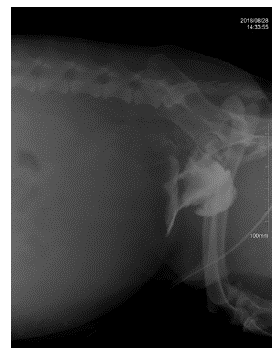

Se realiza ecografía focalizada para trauma abdominal (AFAST, por sus siglas en inglés) (Boysen y Lisciandro 2013) como prueba para el reconocimiento temprano de líquido libre en el abdomen, que en este caso arroja un resultado positivo para la presencia de líquido abdominal en las cuatro ventanas. Posteriormente, se realiza abdominocentesis con el paciente en decúbito lateral derecho para lavado y colecta de líquido peritoneal y se determina el valor de creatinina, cuyo resultado es de 8 mg/dl. Se lleva a cabo un lavado peritoneal con cloruro de sodio 0,9% con el fin de estabilizar al paciente y luego se procede a realizar una radiografía simple (figura 1), una uretrocistografía retrograda (figura 2) con medio de contraste positivo, en este caso iopramida (Ultravist®), en la cual se observa la disrupción uretral y zonas radiopacas en abdomen compatibles con la presencia de medio de contraste en el abdomen caudal, cuyo resultado es positivo para ruptura uretral. Se toman muestras de sangre para cuadro hemático y química sanguínea (ALT, creatinina, potasio, albúmina, calcio) en el que se observan como anormalidades el aumento de creatinina en valores de 2,5 mg/dL y anemia normocítica hipocrómica. No fueron autorizadas la totalidad de los exámenes solicitados. Se realiza un electrocardiograma en el cual no se encuentran anormalidades. Se sugiere la realización de laparotomía exploratoria para verificar daños adyacentes y ubicar y reparar el sitio exacto donde se produjo el rompimiento del tracto urinario inferior.

Proyección latero-lateral izquierda/ derecha de abdomen. En la imagen se observa pérdida de la diferenciación del contorno de los órganos abdominales, densidad radiopaca compatible con líquido libre en el abdomen.

FIGURA 1: Proyección latero-lateral izquierda/ derecha de abdomen. En la imagen se observa pérdida de la diferenciación del contorno de los órganos abdominales, densidad radiopaca compatible con líquido libre en el abdomen.

Fuente: elaboración propia.